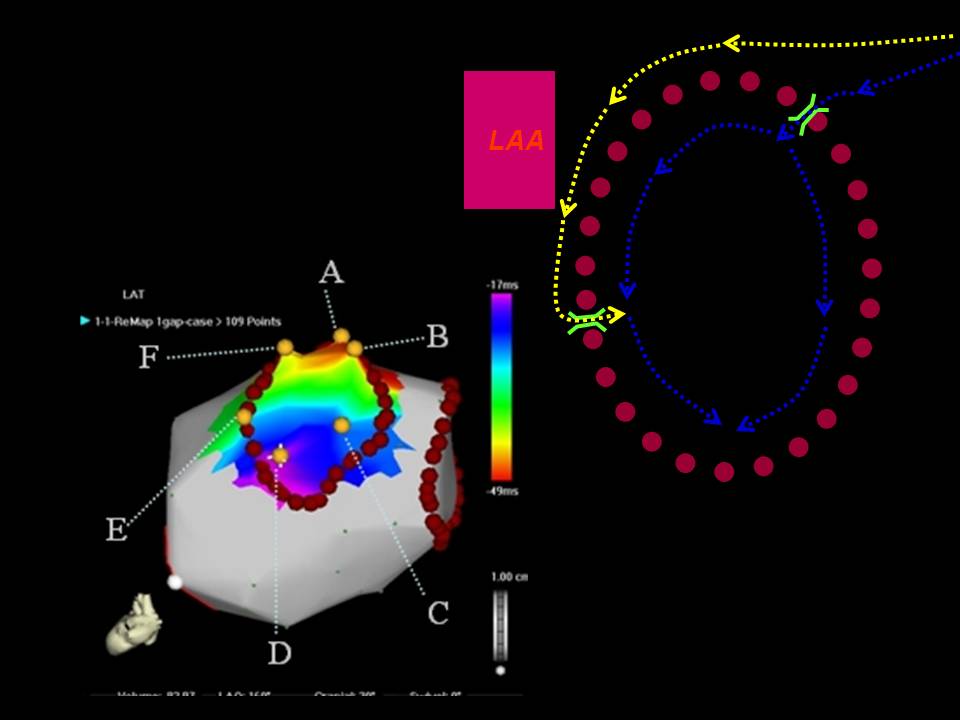

肺静脉隔离术难点